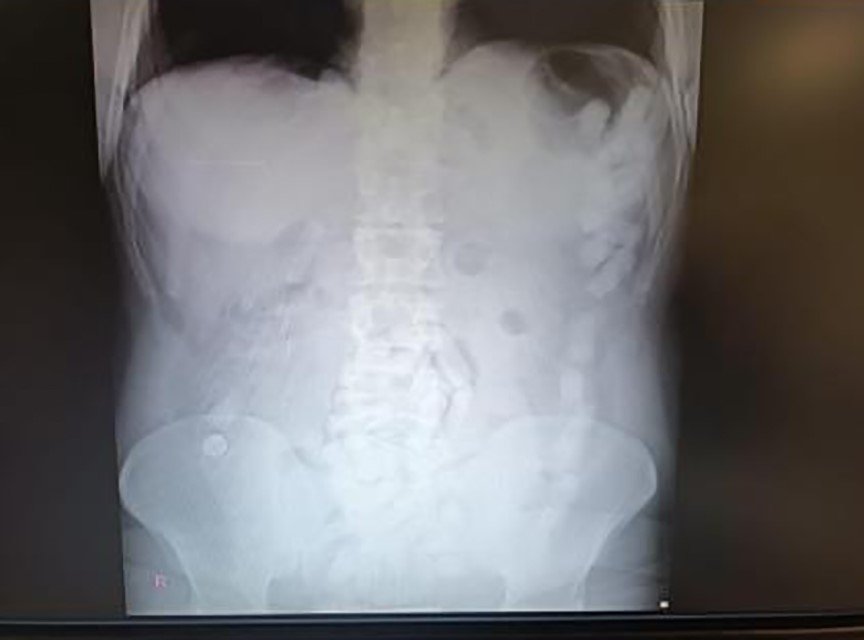

Kayseri'de polis ekipleri tarafından gözaltına alınan şahsın midesinden çıkan 100 kapsülde toplam 729 gram uyuşturucu madde olduğu belirlendi.

Edinilen bilgiye göre, Kayseri İl Emniyet Müdürlüğü Narkotik Suçlarla Mücadele Şube Müdürlüğü ekipleri yabancı uyruklu bir şüphelinin ülkeye giriş yaparak Kayseri'ye geleceğini tespit etti. Şahsı takibe alan ekipler, yerini tespit ettikten sonra operasyon düzenledi. Kayseri Şehir Hastanesinde ultrason çekimi ile yapılan kontrolde şahsın midesinde çok suyada kapsül olduğu tebpit edildi. YApılan operasyonla şahsın midesinden çıkarılan 100 adet kapsülün içerisinde 729 gram uyuşturucu madde ele geçirildi. İşlemlerinin ardından adliyeye sevk edilen şüpheli, çıkarıldığı mahkemece tutuklanarak cezaevine gönderildi.